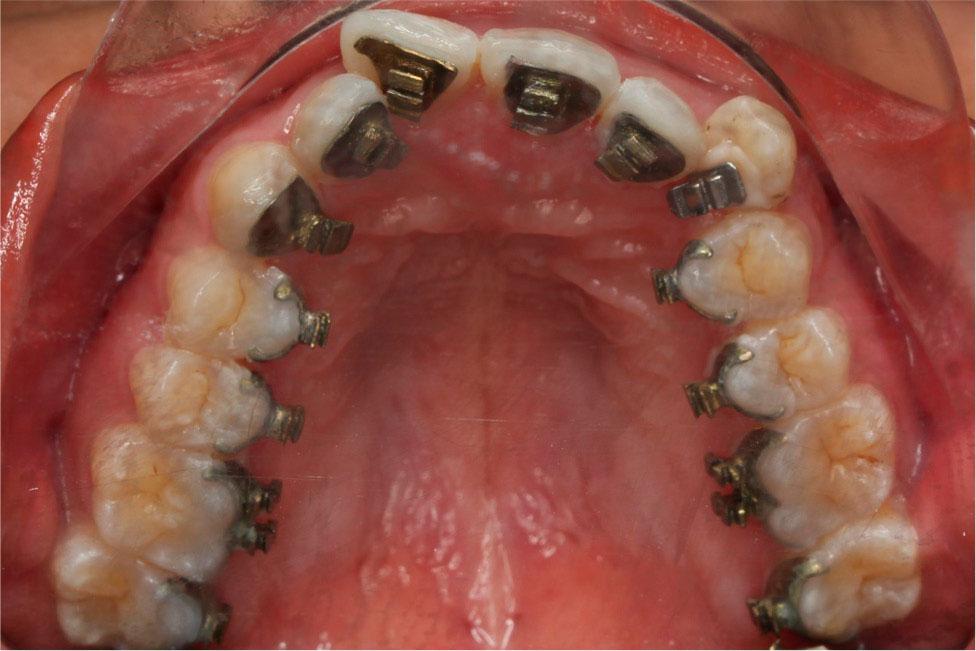

Figure 5.